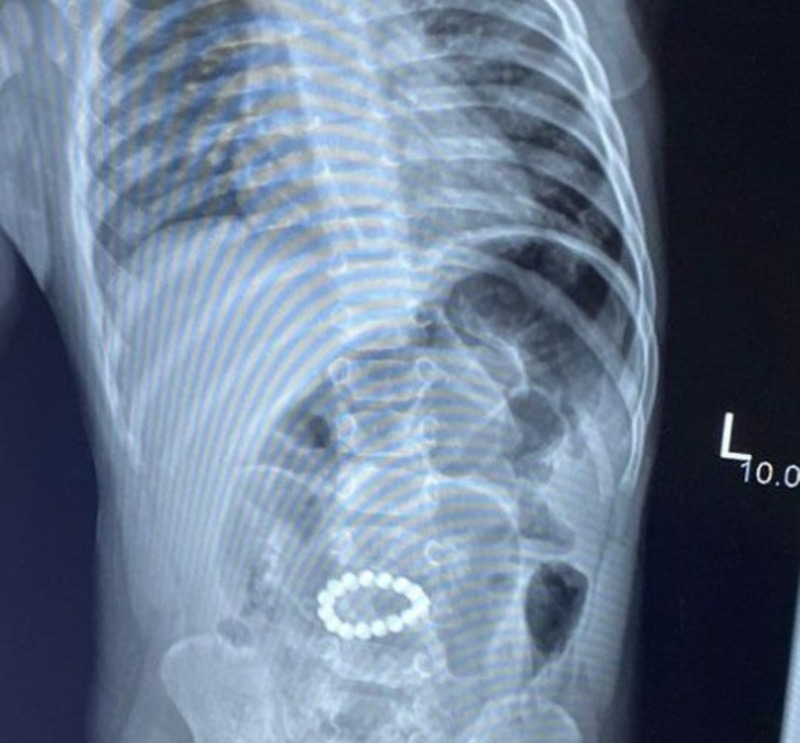

Врачи Областной детской клинической больницы имени Н. Н. Силищевой столкнулись с опасным случаем. Мальчик поступил к ним с симптомами острой кишечной непроходимости. Оказалось, что два дня назад он проглотил 16 магнитных шариков, которые нашёл в доме.

Магниты соединились внутри желудка и образовали кольцо. Состояние малыша было тяжёлым, отмечались слабость, вялость, отсутствие аппетита и стула.